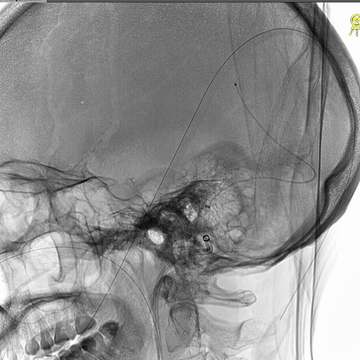

右侧颈动脉造影(正侧位):上矢状窦和直窦未见显影;右侧横窦和乙状窦少许显影。

左侧颈动脉造影(正侧位):上矢状窦前部少许显影,直窦未见显影,左侧横窦和乙状窦显影纤细。